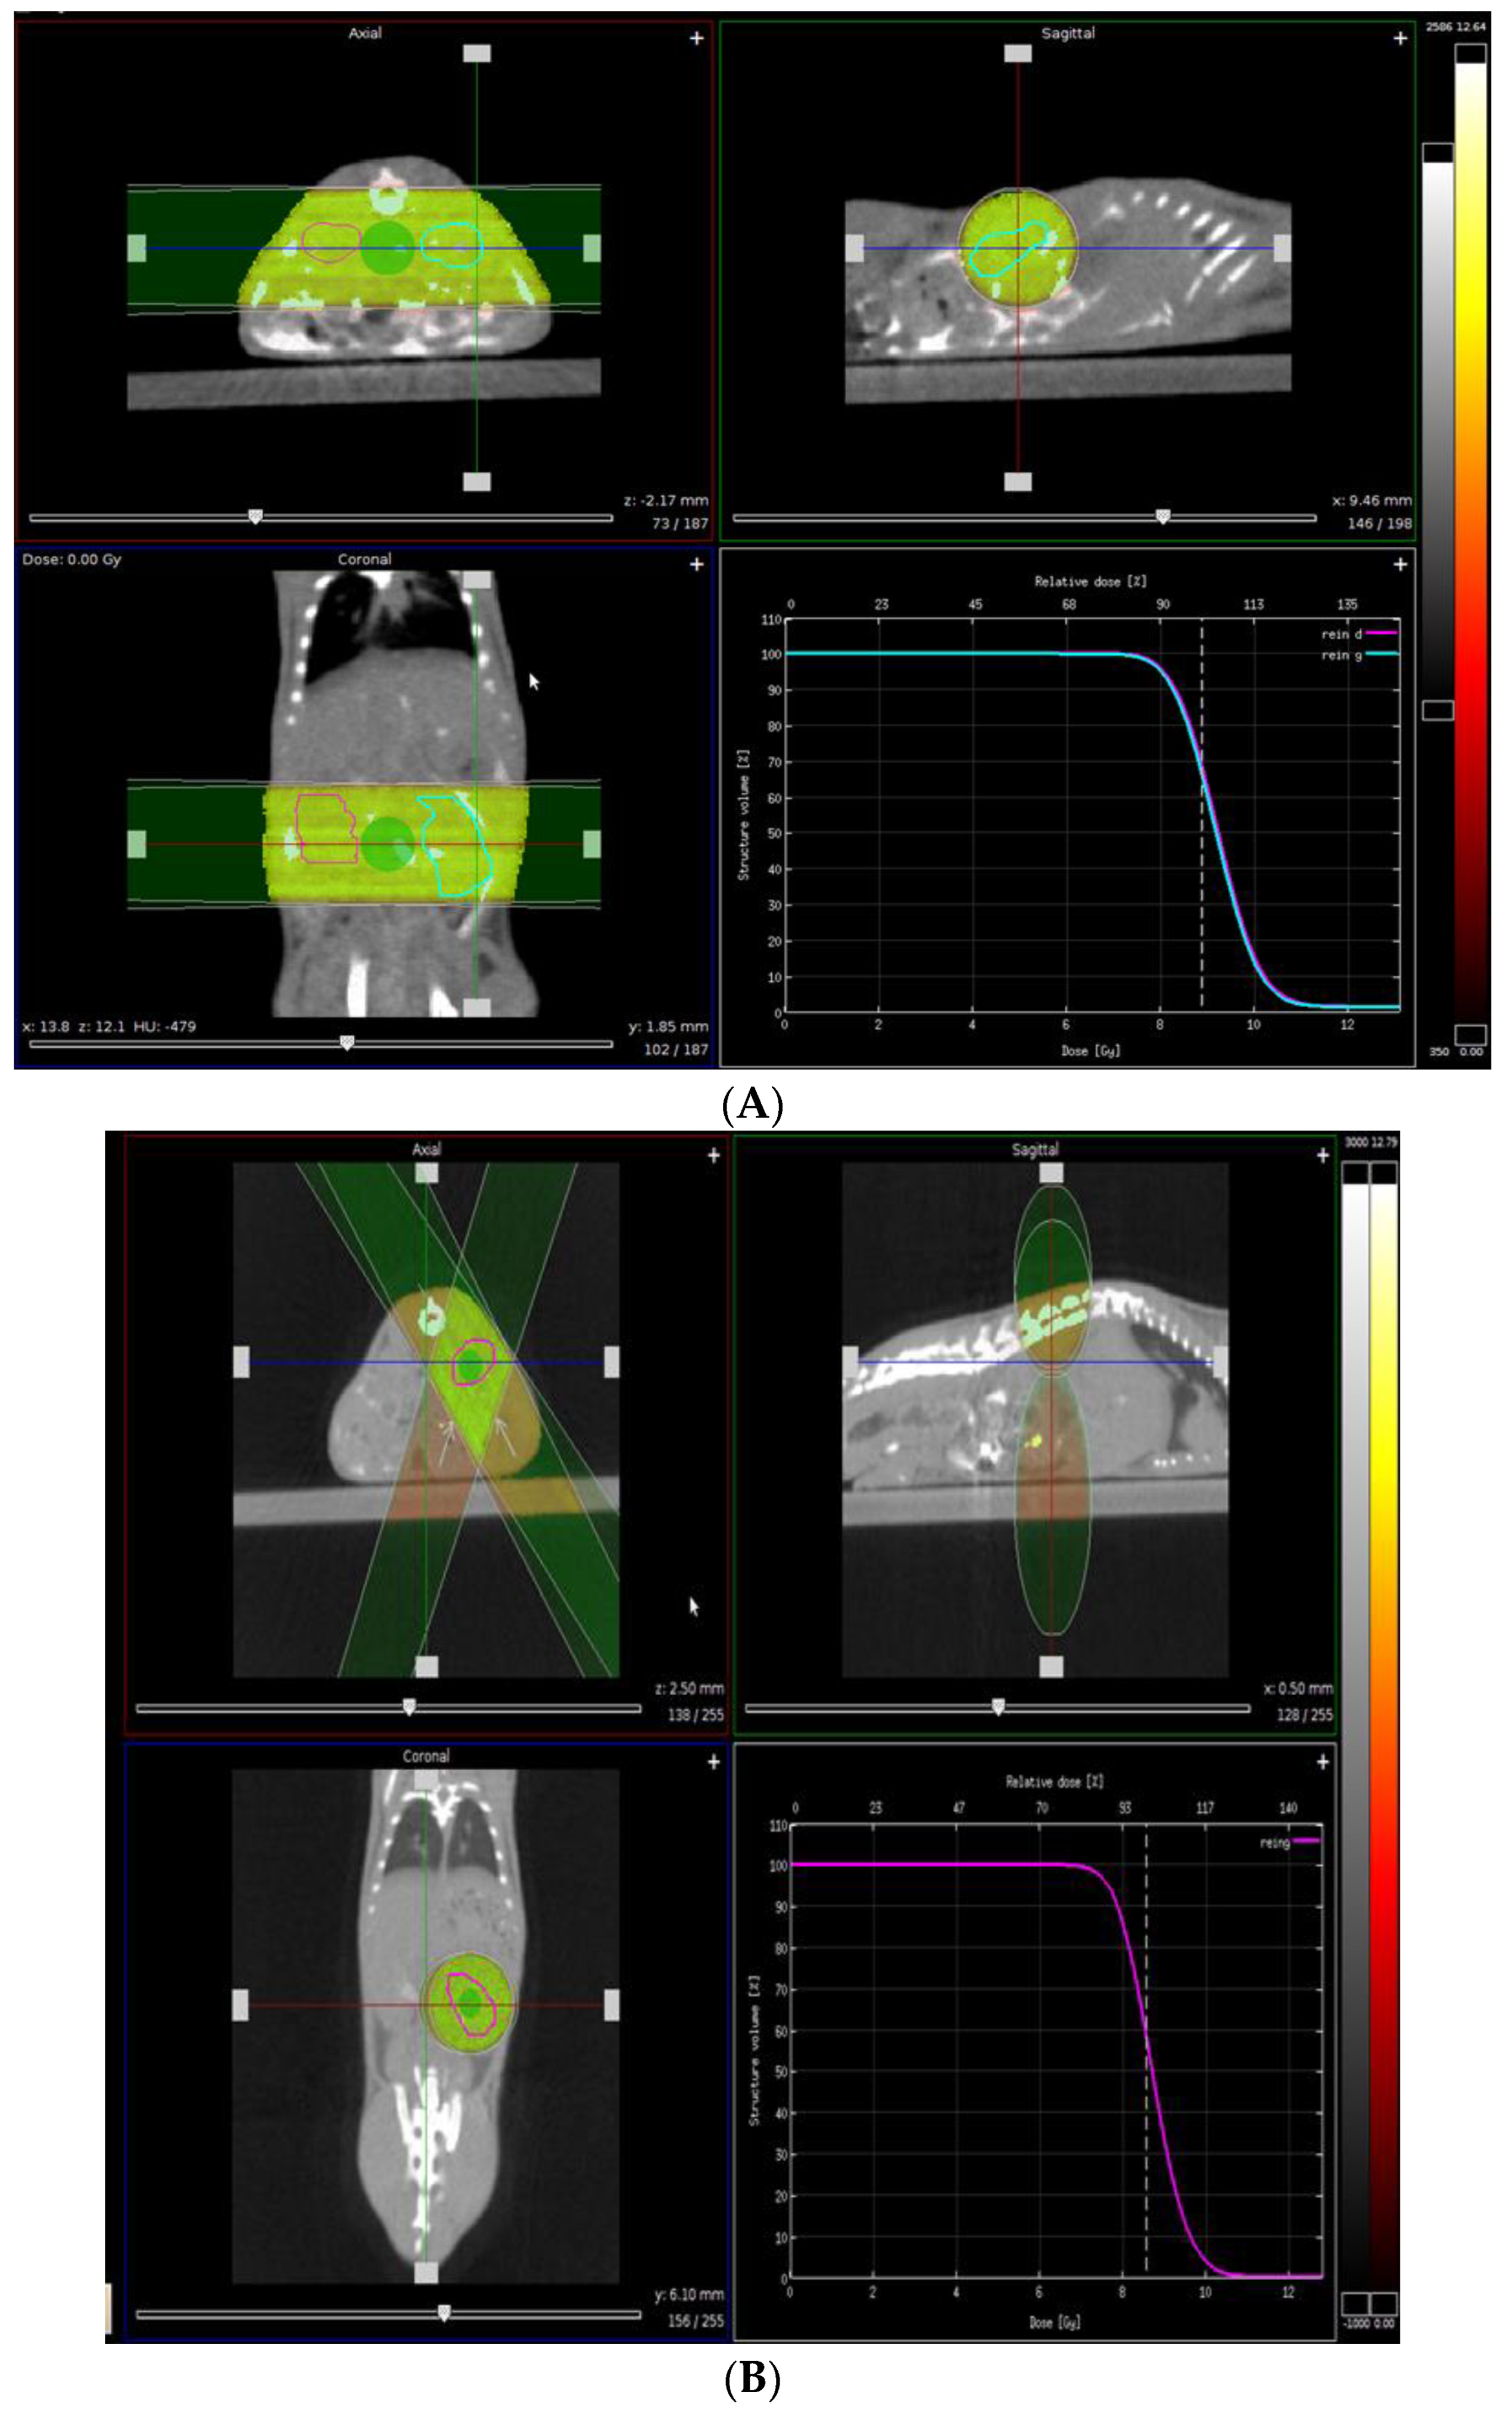

- Verhaegen, F.; Granton, P.; Tryggestad, E. Small animal radiotherapy research platforms. Phys. Med. Biol. 2011, 56, R55–R83. [Google Scholar] [CrossRef] [PubMed]

- Lallemand, F.; Chiver, I.; dos Santos, E.B.; Ball, G.F.; Balthazart, J. Repeated assessment of changes in testes size in canaries by X-ray computer tomography. Gen. Comp. Endocrinol. 2021, 310, 113808. [Google Scholar] [CrossRef]

- Lallemand, F.; Leroi, N.; Blacher, S.; Bahri, M.A.; Balteau, E.; Coucke, P.; Noël, A.; Plenevaux, A.; Martinive, P. Tumor Microenvironment Modifications Recorded with IVIM Perfusion Analysis and DCE-MRI after Neoadjuvant Radiotherapy: A Preclinical Study. Front. Oncol. 2021, 11, 784437. [Google Scholar] [CrossRef]